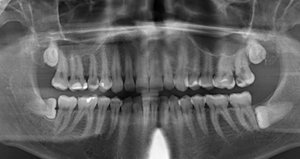

В течение нескольких месяцев у меня иногда болел зуб, боль была не сильной и проходила самостоятельно, при жевании на стороне зуба болезненность не отмечалась. Когда обратилась к стоматологу, он определил, что больной зуб четвертый сверху, сделал снимок, прочистил каналы и поставил мышьяк, в итоге он удалил мне нерв. Прочитала в инете, что нерв удаляют только при крайних случаях, когда боль невыносимая или зуб темнеет.

Действия врача абсолютно верные, у зуба диагноз пульпит, и его необходимо было депульпировать, в противном случае вы могли заработать себе хроническое воспаление (периодонтит).